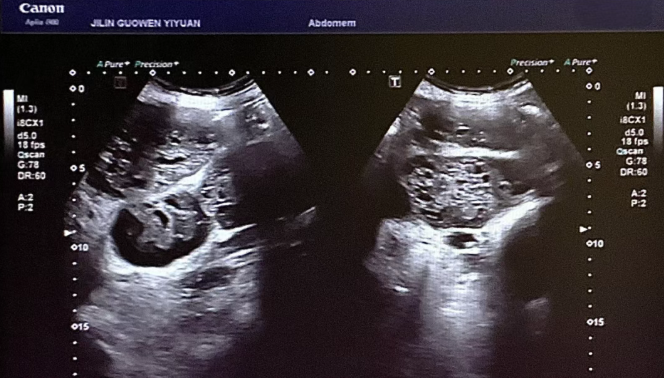

患者錢女士(化名),65 歲,因有高血壓病史而定期進(jìn)行體檢。在超聲檢查時(shí),醫(yī)生發(fā)現(xiàn)其腎臟存在占位性病變。超聲科團(tuán)隊(duì)借助高分辨率超聲成像技術(shù),清晰地觀察到腎臟內(nèi)的異常回聲區(qū),再結(jié)合血流信號(hào)分析,高度懷疑該病變可能為惡性腫瘤。為進(jìn)一步明確診斷,團(tuán)隊(duì)在超聲引導(dǎo)下進(jìn)行精準(zhǔn)穿刺,獲取病理組織。最終,病理報(bào)告確診該病變?yōu)?“小圓細(xì)胞惡性腫瘤”。

小圓細(xì)胞惡性腫瘤是一類較為少見(jiàn)的惡性疾病,常見(jiàn)于兒童及青少年,而發(fā)生在老年患者腎臟的情況則更為罕見(jiàn)。此類腫瘤具有很強(qiáng)的侵襲性,早期診斷對(duì)于治療方案的制定以及患者的預(yù)后都至關(guān)重要。錢女士雖然沒(méi)有出現(xiàn)典型癥狀,腹部查體也未觸及包塊,但得益于超聲科的細(xì)致檢查,病灶被及時(shí)發(fā)現(xiàn),這為后續(xù)的治療贏得了寶貴時(shí)間。